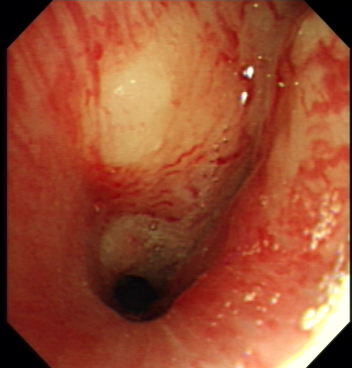

Once patients are suspected to have lung cancer or TB with X-ray or CT, bronchoscopy is followed-up from radiological imaging. Bronchoscopy is used as one of the invasive tool to directly detect the disease since 1960s [4]. Fig. 1 shows an example of normal tissue, TB and cancer. In bronchoscopy, usually we can observe that invasive TB, the lumen surface suffers from inflammatory change with hyperemia, edema and ulceration. Lung adenocarcinomas grow extraluminally and lead to lumen stenosis without affecting mucosal surface of lumen. Therefore, the mucosal surface of lumen is relatively smooth. However, squamous lung cancers always form intruding nodules and are difficult to be differentiated from TB granuloma visually. Computational aid is therefore needed in bronchoscopy, especially for lesion discrimination and targeting. Accurate targeting the disease area could significantly reduce the biopsy trauma and increase diagnostic accuracy [5].

Figure 1: A bronchoscopy image of normal (a), TB (b) and cancer (c)